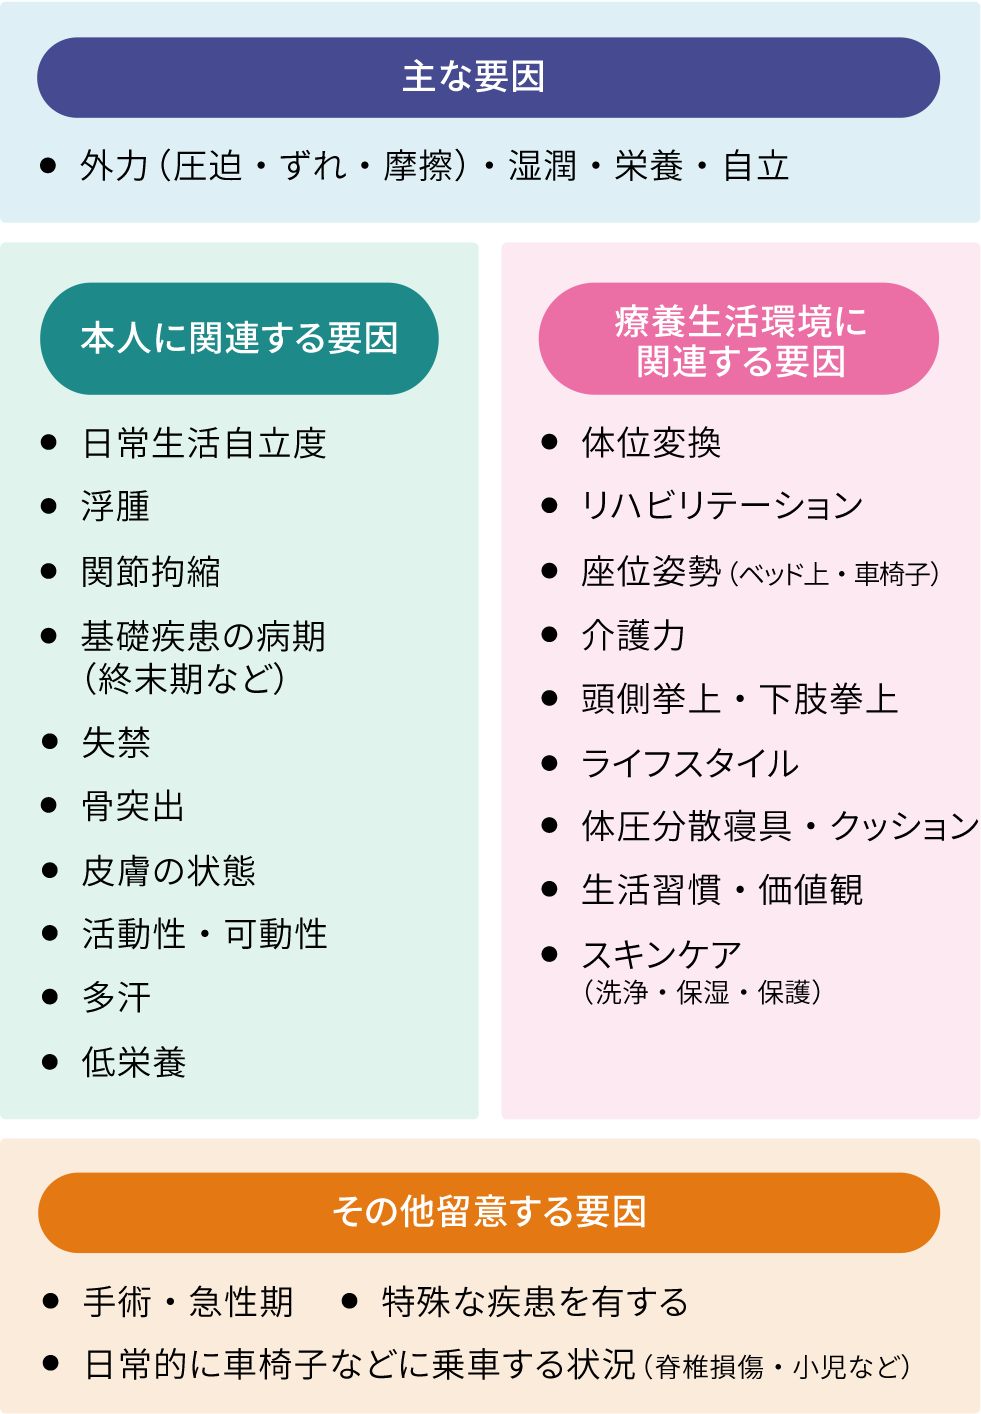

褥瘡の原因・好発部位・進行度分類・褥瘡予防や対策の記録方法介護健康福祉のお役立ち通信。

褥瘡とは?定義・原因・看護ケアについて解説レバウェル看護 お役立ち情報。

褥瘡 じょくそう 病気の知識介護の知識訪問看護・24時間の在宅看護等のサービスを自費で! ナースアテンダント。

褥瘡とは?読み方や原因、初期症状や見分け方など網羅的に解説 - LIFULL 介護 ライフル介護。

褥瘡 床ずれ とは? 原因と症状、予防法についてHeartPlus ハートプラス。

褥瘡 床ずれ とは?症状と処置方法認知症ポータルサイト「テヲトル」。

褥瘡の予防と観察ポイント見て!わかる!病態生理と看護 花子のまとめノート。

褥瘡とは?定義・原因・看護ケアについて解説レバウェル看護 お役立ち情報。